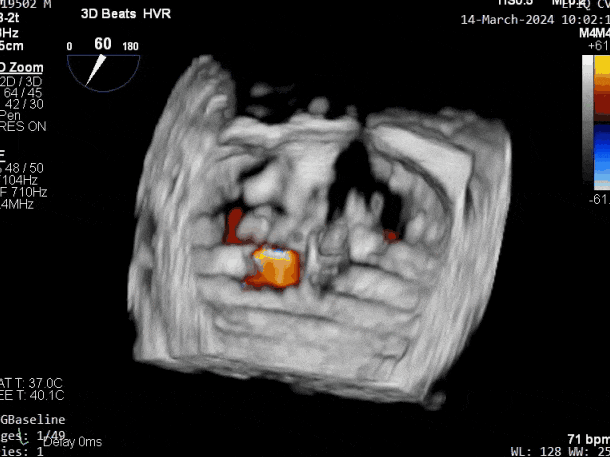

释放瓣膜夹后评估,二尖瓣呈双孔,外侧仍有残余反流

第二个瓣膜夹释放后评估,二尖瓣呈双孔,外侧仍有残余反流

第三个瓣膜夹释放后评估,释放后评估,二尖瓣呈双孔,组织桥张力合适,瓣膜夹轴向与二尖瓣闭合线垂直,无残余反流

肺静脉血流频谱恢复为收缩期正向

2. 本例患者外院超声心动图考虑二尖瓣前叶脱垂,入院后经食道超声心动图明确该患者为二尖瓣后叶活动受限,呈房源性栓系,二尖瓣前叶假性脱垂,超声特征表现为心房功能性二尖瓣反流终末期,呈现出很典型的二尖瓣后瓣环向左室游离壁顶部位移和后叶挛缩表现,同时合并有明显的二尖瓣瓣环扩张、圆形化,左房增大等不利因素,术中通过精准的影像指导和手术操作,成功行TEER,二尖瓣反流程度减轻至微量。